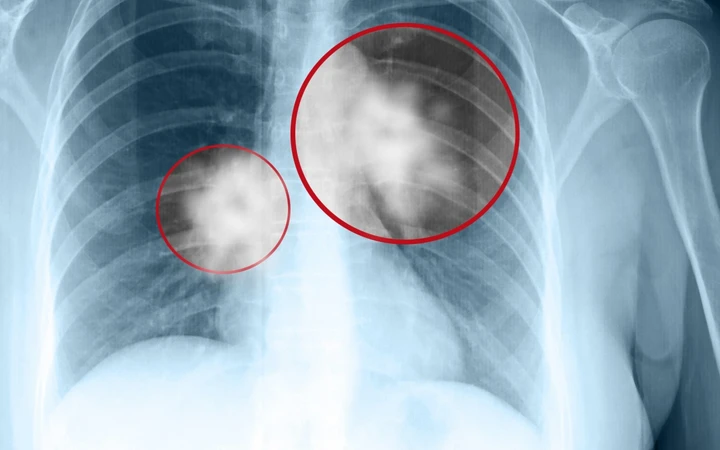

Bài viết trên website Bệnh viện Đa khoa Tâm Anh có sự tư vấn chuyên môn của GS.TS.BS. Ngô Quý Châu cho biết, ung thư phổi (tiếng Anh là Lung Cancer) là loại ung thư khởi phát từ phổi hay còn được gọi là khối u ác tính ở đường hô hấp. Bệnh xảy ra khi một khối u ác tính hình thành trong phổi, phát triển nhanh về kích cỡ dẫn tới xâm lấn, chèn ép các cơ quan xung quanh. Hai lá phổi trong lồng ngực có chức năng hấp thụ oxy khi hít vào và thải carbon dioxide (CO2) khi thở ra.

Ngoài ra, vẫn có trường hợp có thể xuất hiện các khối u phổi lành tính. U lành có về cơ bản có sự khác biệt rất lớn với u ác tính (tế bào ung thư). Tuy nhiên, để xác định chính xác tính chất của khối u, vẫn cần các phương pháp chẩn đoán khoa học và chính xác từ các bác sĩ, chuyên gia y tế.

Ung thư phổi là một trong những căn bệnh ung thư nguy hiểm